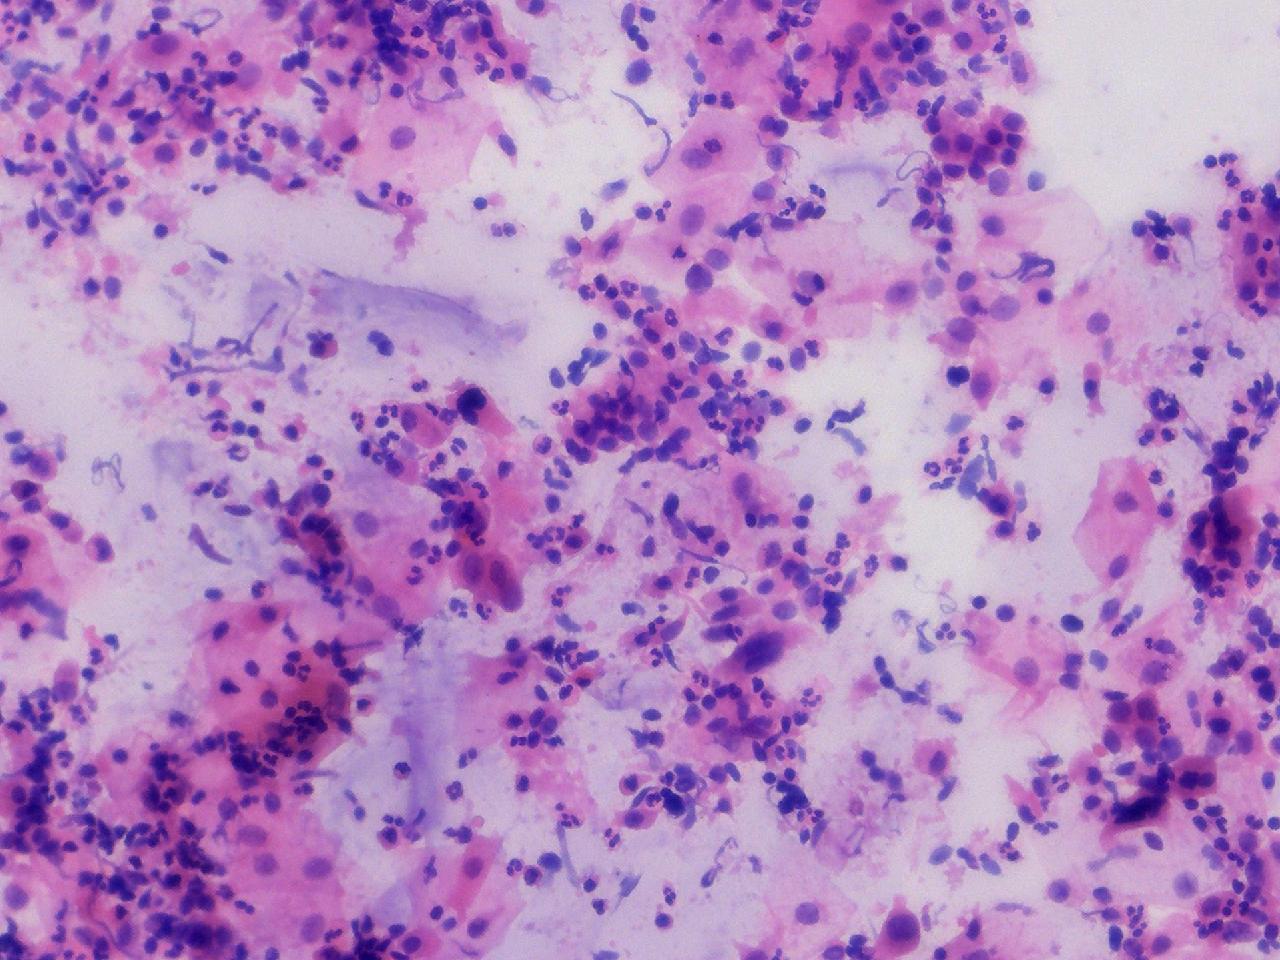

可见较多腺细胞。请教诊断。

性别

女

年龄

55岁

一般病史

绝经2年余,阴道淡血水3月余,子宫肌瘤10余年,HPV不详。

标本类型

妇科TCT

制片方法

离心后,沉降式制片

染色方法

NILM